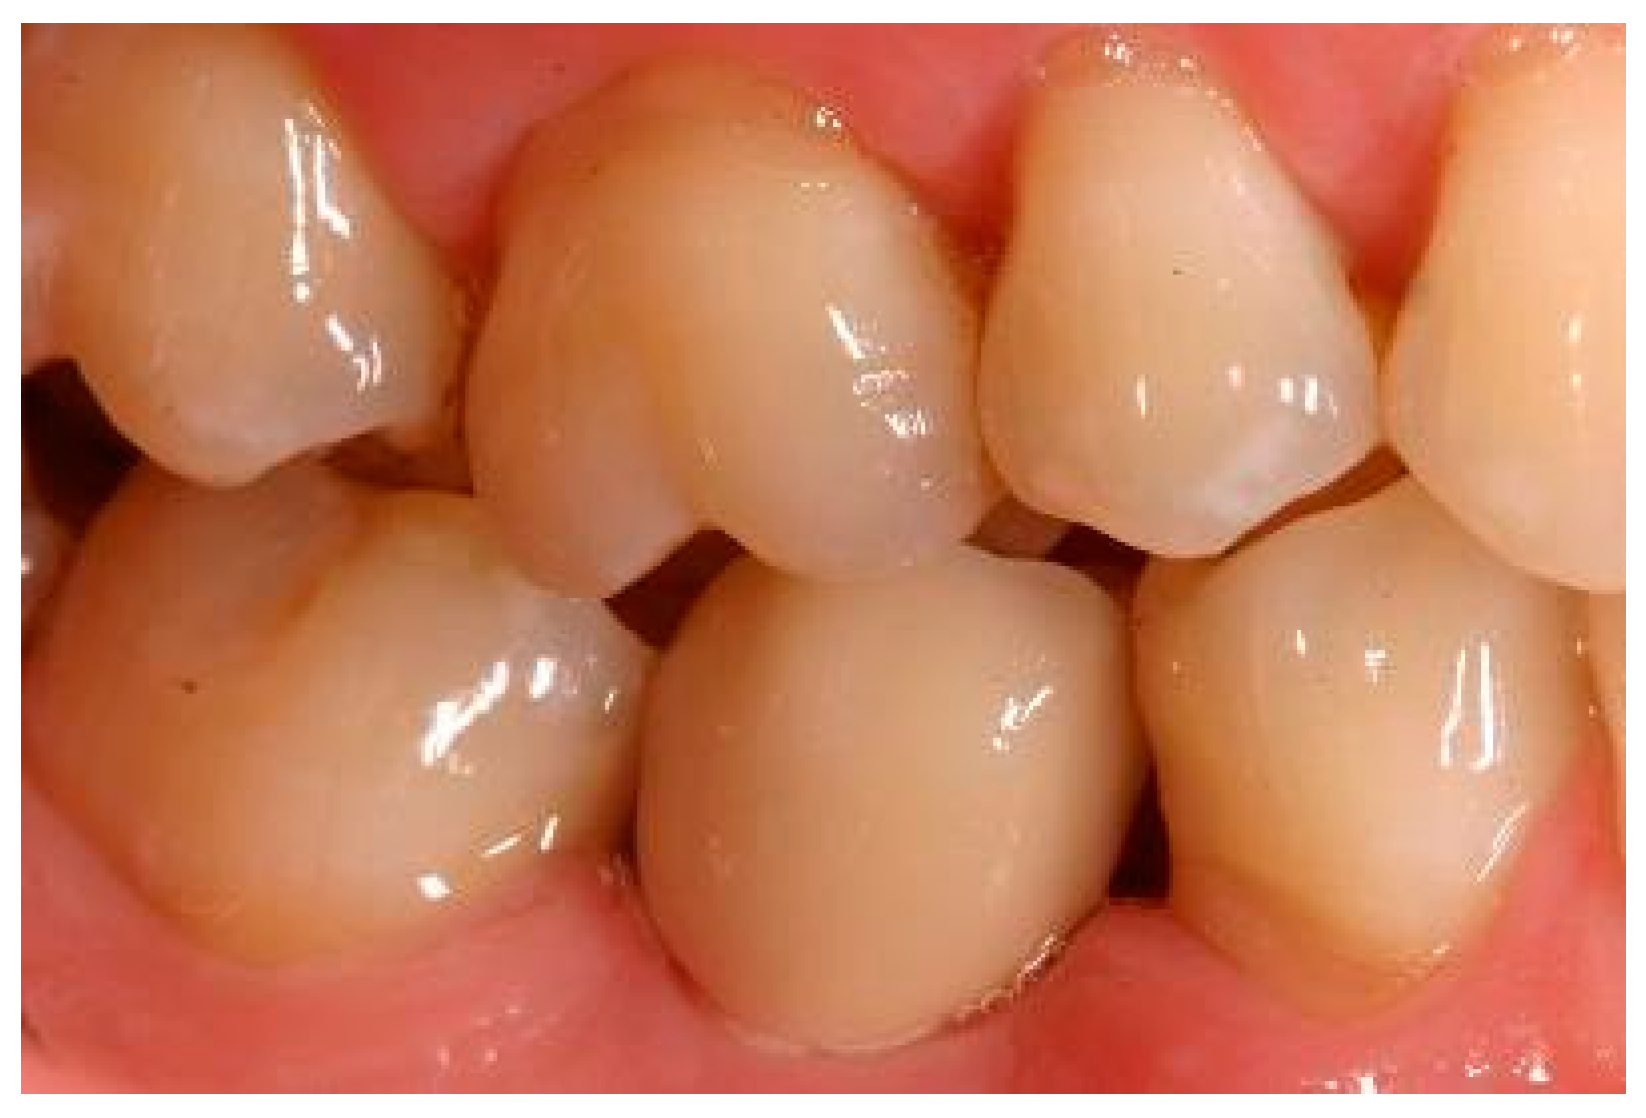

Appendix B. Exemplary Photographs and Radiographs from a Patient at Different Examination Time Points and a More Negative Outcome